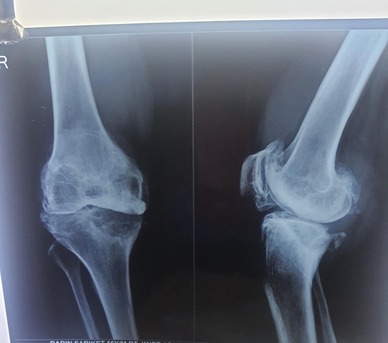

What Is a Fracture?

A fracture happens when a bone breaks partially or completely due to factors like high-force injury, extreme stress, or medical conditions. It causes severe pain, trauma, and swelling and significantly reduces mobility.

Signs You May Have a Fracture?

If you have a fracture, you can have the following:

Severe pain and swelling in an injury area.

Deformity in the affected area.

Difficulty in moving your limbs/body parts.

Bone is openly visible (open fracture)